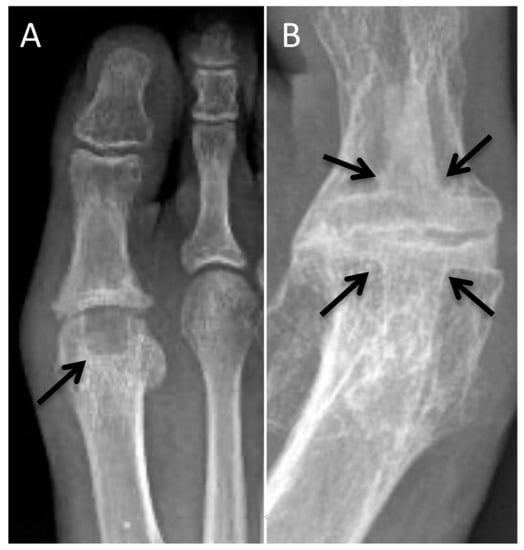

2.10. Second-Metatarsal Shortening

2.11. Calcaneal Osteotomy